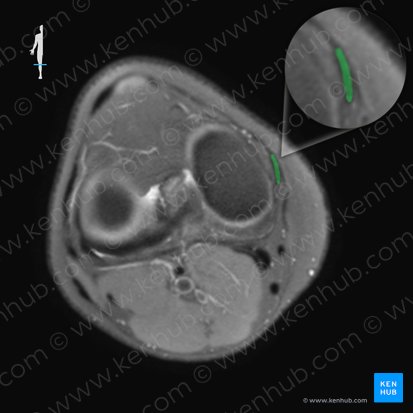

Es ist wichtig, das VKB auch in der axialen Ebene zu überprüfen, wo es am besten auf einem Schnitt auf Höhe der interkondylären Kerbe dargestellt werden kann . Auf dieser Ebene ist das VKB an der lateralen Femurkondyle wie ein schwarzes Band, etwa 1,5 cm im anterior-posterioren Durchmesser zu sehen. Beim Weiterscrollen in Richtung der Tibia sehen wir, dass sich das VKB auffächert und zur medialen Femurkondyle übergeht.

Auf einem Bild in der T1-Sagittalebene sehen wir, dass die Menisken einheitlich signalarm sind und normalerweise als schwarze, schleifenförmige Struktur im Gelenkraum erscheinen. Auf einem axialen Bild hingegen sehen wir den medialen und lateralen Meniskus als schwarze, halbkreisförmige Strukturen, direkt unterhalb der medialen bzw. lateralen Femurkondyle. Wir sollten auf eine erhöhte Signalintensität in den Menisken achten. Ein hyperintenses Signal, welches das Signal des Gelenkknorpels erreicht, kann auf einen Meniskusriss oder eine degenerative Veränderung hinweisen.

Auf einem Schnitt durch die interkondyläre Kerbe in der axialen Ebene können wir den Ursprungspunkt des MCLs finden. Dieser erscheint als kurzes, niedriges Signalband nahe der medialen Seite der Femurkondyle. Wenn wir weiter nach unten scrollen, können wir das MCL bis zu seinem Ansatz an der Tibia verfolgen.

Betrachtet man das LCL in der Axialebene auf einem Schnitt durch die interkondyläre Kerbe, so kann man ihren Ursprung als ovales schwaches Signal in der Nähe des posterioren Aspekts der Femurkondyle erkennen. Wenn man nach unten scrollt, kann man dem LCL folgen, wie es an der anterolateralen Seite des Fibulakopfs ansetzt.

Die Patellasehne ist die distale Fortsetzung der Quadrizepssehne, die an der Spitze der Patella (Apex patellae) beginnt und an der Tuberositas tibiae ansetzt. Wir können die Patellasehne in einem Schnitt durch das Tibiaplateau in der Axialebene sehen. Diese erscheint als ein dunkles, homogenes Band mit geringer Signalintensität, das die Patella bedeckt. Auf dieser Ebene ist auch eine große Ansammlung von Fettgewebe zu erkennen, das sogenannte infrapatellare Fettpolster, zu sehen, das sich unterhalb der Patella in der Tiefe im vorderen Teil des Kniegelenks befindet.

Die Retinaculum patellae laterale und mediale werden am besten in der Axialebene in einem Schnitt durch das Femoropatellargelenk dargestellt. Das Retinaculum patellae mediale und laterale sind Verlängerungen des M. vastus medialis und M. vastius lateralis, die sie mit den Rändern der Patella (Margines superior, medialis und lateralis) verbinden.